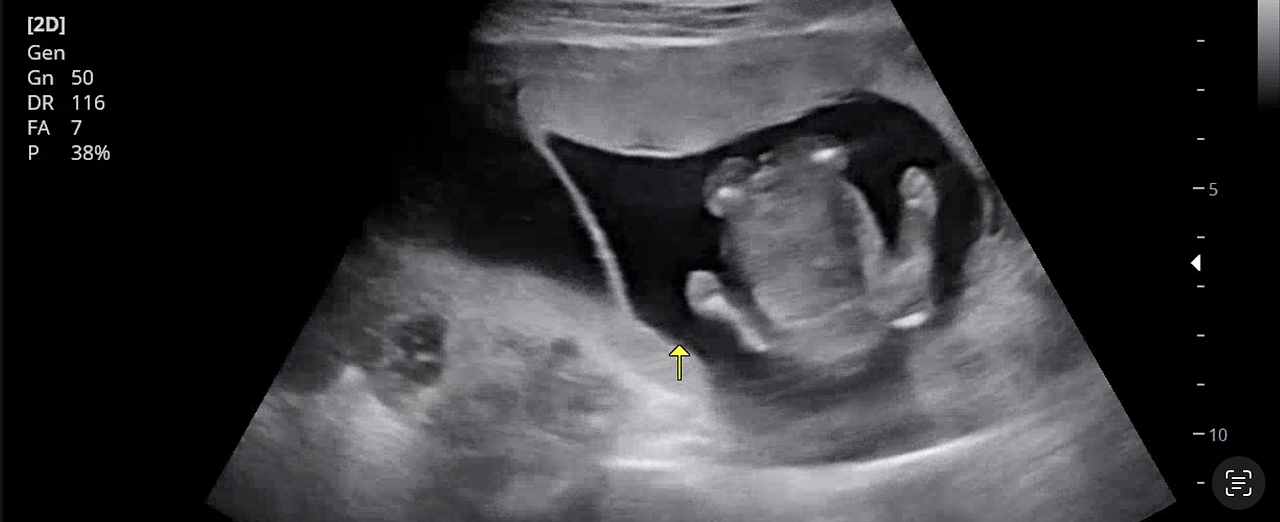

이제는 모모와 봉봉이의 성별이 궁금해지는 시기. 보통은 14주쯤 의사 선생님이 성별을 알려준다고 하는데 아직도 소식을 듣지 못했다. 지난주 주말에 병원에 갔을 때 선생님은 분명 성별을 알 수 있었을 텐데 돌려서도 이야기를 해주지 않았다. 덕분에 아내와 나는 마지막에 촬영한 초음파 영상을 몇 번이나 돌려봤는지 모른다. 각자 휴대폰으로, 노트북으로 여러 번 돌려보니 둘 다 남자아이일 가능성이 높아 보인다. 아내와 나는 잠깐 실망을 했지만, 건강하게만 나온다면 성별이 중요하진 않다. 쌍둥이 육아에 있어서는 다른 성별보다는 같은 성별일 경우, 더 유대감을 가질 수 있다고 하니 그런 면에서도 다행이라는 위안을 삼는다. 말도 못 하는 아이들이 서로 같이 뛰어노는 상상을 하니 지금부터도 웃음이 난다.